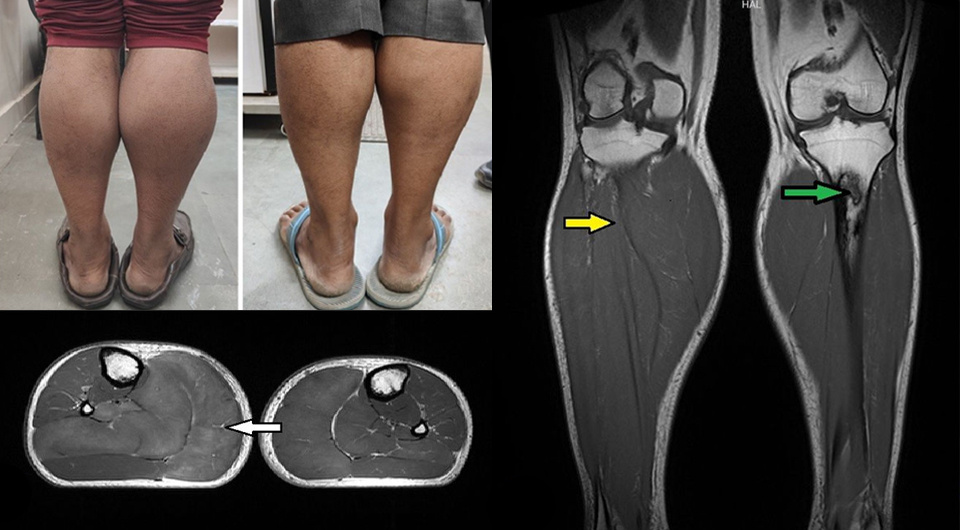

При росте 165 сантиметров мужчина весил 70 килограмм. При поступлении пульс был 69 ударов в минуту, артериальное давление — 116/86 миллиметров ртутного столба. Высшая нервная деятельность была нормальной, обследование сердечно-сосудистой, дыхательной и пищеварительной систем — без особенностей. При осмотре нижних конечностей наблюдались выраженные изолированные отеки обеих икроножных мышц, кожа над ними была плотно натянутой, сухой, огрубевшей и шелушащейся. Наибольший обхват правой голени составлял 43, левой — 38 сантиметров. При проверке коленного рефлекса отмечалась замедленная релаксация мышц.

Осмотр и пальпация щитовидной железы были без особенностей. На УЗИ была видна неоднородная структура с неоднородными (преимущественно гиперэхогенными образованиями) при гладких краях и нормальной васкуляризации железы, что характерно для тиреоидита. ЭКГ показала нормальный синусовый ритм, эхокардиограмма — отсутствие патологических изменений с нормальной фракцией выброса (55 процентов). На МРТ ног визуализировались увеличение объема и отек икроножных и камбаловидных мышц, а также инфаркты большеберцовой кости. На основании данных обследования пациенту поставили диагноз тяжелого гипотиреоза с псевдогипертрофией мышц голеней.